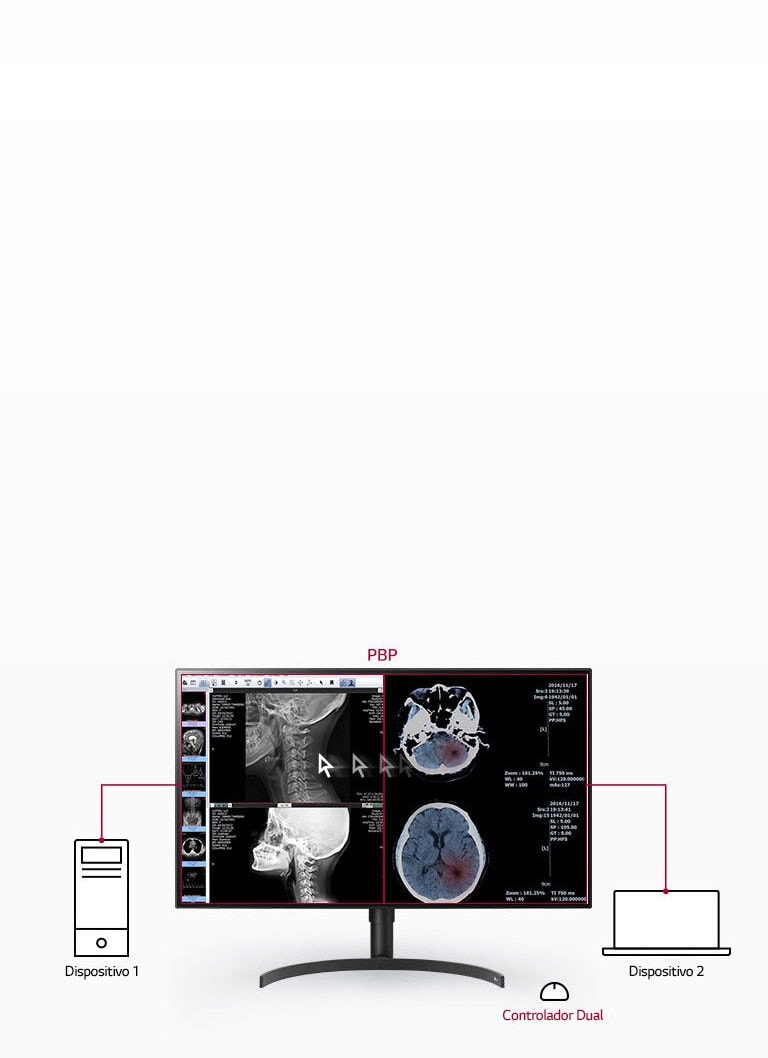

PBP

2PBP

Control Dual

Si